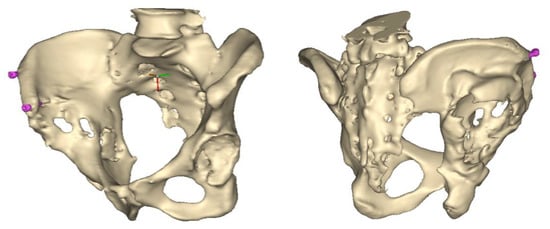

A 3D pelvis reconstruction allowed further processing using the Mimics Innovation Suite (Materialize NV, Leuven, Belgium), which is an engineering software package that enables 3D medical imaging and surgical-related planning. So, the design of the patient-specific aiming device was based on a 3D reconstruction of the patient’s own anatomy. After importing and transforming the two-dimensional Digital Imaging and Communications in Medicine (DICOM) standard file, the radiation absorption range was selected using the windowing method for spatial imaging of the reliable bone structure (Figure 1).

Figure 1.

3D images of the mask that appeared when the CT scans were threshold and the spatial model derived from it. The heads of the implanted screws are displayed in purple.

The mask obtained in this way contained only the real bone volume relevant to the task, in our case, the pelvis with significant bone defects and the femur on the same side.

After smoothing the mask to remove surface roughness due to the low resolution of the diagnostic imaging, the hemi-pelvis with significant bone defect was printed using a Stratasys F270 (Stratasys Ltd., Rehovot, Israel) fused deposition modeling (FDM) 3D printer. A square grip was attached at the sacrum in such a way that the model could be exposed on a stand and used as a reference to facilitate the spatial orientation in the OR.

The aiming devices were built in the 3-Matic (Materialize NV, Leuven, Belgium) medical-related CAD design software. After importing the hemipelvis, the most suitable cup diameter could be determined. This requires the editing of the largest sphere that can be modeled into the damaged side of the iliac crest.

Therefore, the aiming device was first validated on a virtual 3D model. The entry and exit points and the path it takes through the bone were clearly visible in the design software, using the semi-transparent display mode. Then, the 3D-printed targeting model was fitted to the previously printed hemipelvis with its actual dimensions. The accuracy of the aiming was also verified by test drilling. The assembled model was then available to the surgeon in the OR for visual inspection, which helped to ensure spatial orientation (Figure 3).